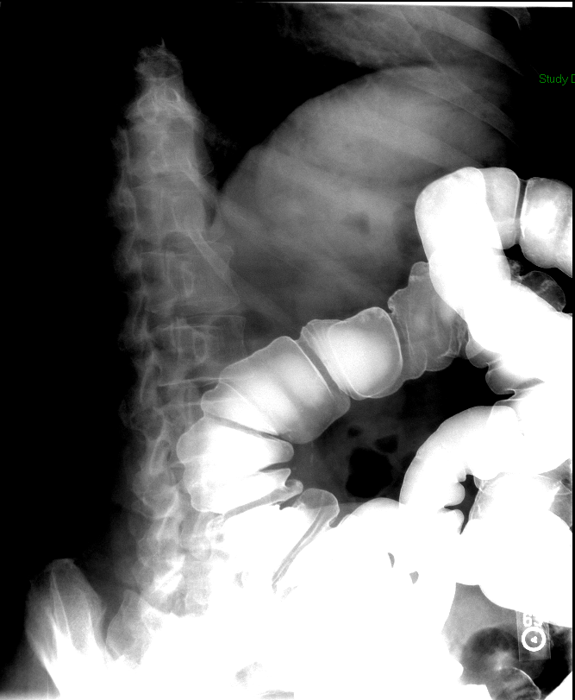

- The technologist will obtain radiographs at 30, 45, and 60 minutes after the initial administration of barium. If the column of contrast material has not reached the large bowel on the 60 minute film, the technologist will obtain images every 30 minutes until contrast can been seen in the cecum

(key image 3)

(key image 4)

(key image 5).

- Obtain images of the terminal ileum and the ileocecal valve filled with contrast material

(key image 6)

(key image 7)

(key image 8)

(key image 9)

(key image 10).

- Obtain spot images of the remainder of the small bowel

(key image 11)

(key image 12)

(key image 13)

(key image 14).

- Obtain images of all four quadrants. Use the compression paddle to separate loops of small bowel from each other.